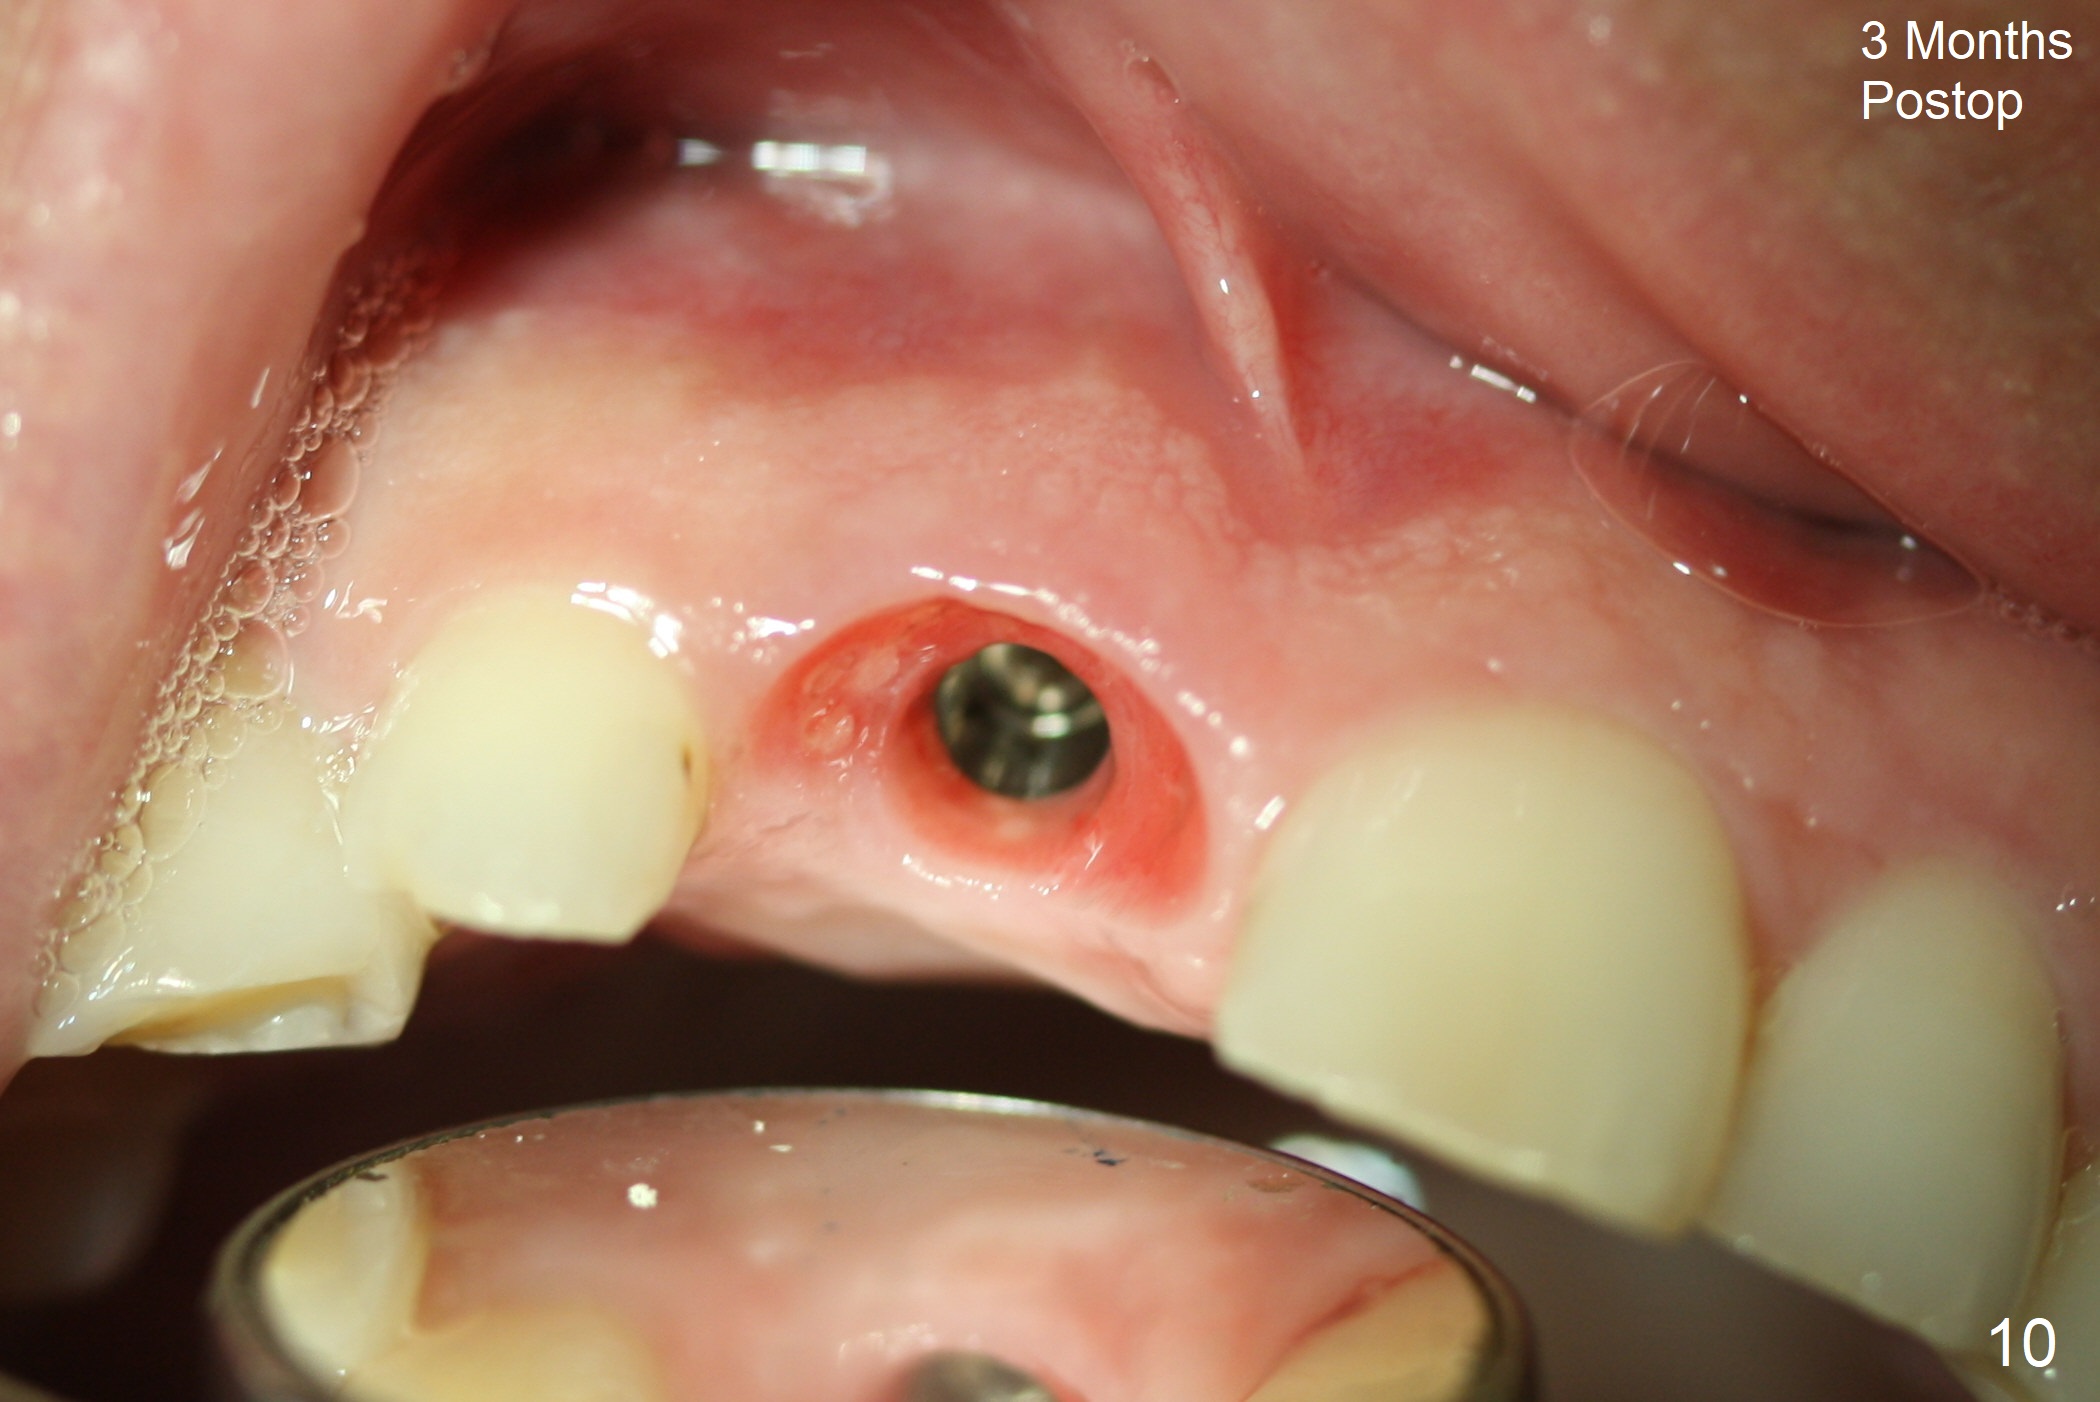

The buccal gingiva at #8 is erythematous (Fig.1: *), which is associated with the tooth fracture line (Fig.2 with granulation tissue: *). The buccal plate remains intact. Osteotomy is initiated in the palatal wall of the socket (Fig.3,4). The initial osteotomy depth is 16 mm (Fig.5); the trajectory is going to be adjusted as shown by arrows. The trajectory improves when a 3.8x15 mm dummy implant is placed (Fig.6). The definitive implant (3.8x16 mm) appears to be placed at an appropriate level (Fig.7). A 4.5x3 mm temporary abutment is inserted for an immediate provisional. As routine, Vera Graft is placed in the buccal gap. The buccal gingival erythema reduces without tenderness 1 week postop (Fig.8). Although the provisional is unstable, there is no bone loss 2 months 20 days postop (Fig.9). Because of the loose provisional (partial detachment from the underlying temporary abutment), impression is taken earlier (3 months postop, Fig.10,11). Due to the pointed abutment tip, the crown is redone 3 times. By the time of cementation (nearly 5 months postop), the socket appears to have healed (Fig.12).